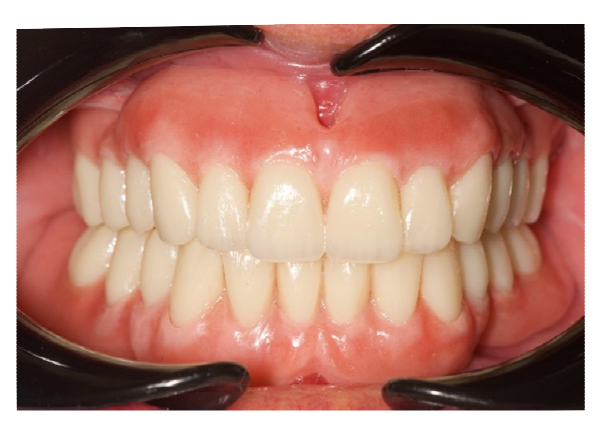

Диагностическая терапия была направлена на переобучение пациента, который был беззубым в течение нескольких лет. Были запланированы немедленные, диагностические, полные съемные верхние и нижние протезы. Этот первый этап был полностью аналогичным. Предварительные слепки были сняты с помощью альгината для отливки учебных моделей. Окончательные слепки были сняты с помощью индивидуального ложки для слепков. Центрическая связь и вертикальное измерение окклюзии были зафиксированы с использованием маневра Досона и фонетических звуков соответственно. Мастермодели были установлены в полу-регулируемом артикуляторе с помощью лицевой дуги. После этого немедленный съемный протез был завершен с использованием задних зубов с углом наклона бугорков 0 градусов, чтобы позволить перемещение нижней челюсти. В день первой операции пациенту была проведена местная анестезия (4% артикаин с адреналином 1/100,000, Septanest, Septodont, Матаро, Испания). Все оставшиеся зубы были аккуратно удалены, и костный гребень был моделирован. Немедленный, диагностический, полный съемный протез был затем передан. Основание и окклюзия были отрегулированы, и пациент наблюдался каждые две недели в течение четырех месяцев. На каждом осмотре окклюзия регулировалась для нахождения правильного положения нижней челюсти, без изменения вертикального измерения окклюзии. Через четыре месяца пациент был доволен новой функцией и эстетикой. Следующим шагом было планирование установки имплантатов, ориентированных на протезирование. Существующие, диагностические, функционализированные съемные протезы были дублированы и использованы в качестве индивидуальных ложек для слепков для снятия новых окончательных слепков. Для установки мастермоделей и дубликатов в артикуляторе использовалась техника перекрестного монтажа, сохраняя центровую связь и актуальное вертикальное измерение окклюзии. Наконец, новые временные протезы были изготовлены с полностью анатомической окклюзией (Рисунок 3). На этом этапе была обеспечена двусторонняя сбалансированная окклюзия у всех леченых пациентов.

На этом этапе все последующие шаги, от планирования имплантации до доставки окончательных реставраций, были выполнены полностью в цифровом формате. После изготовления новых протезов пациенту был выполнен КТ-сканирование верхней и нижней челюстей по модифицированной технике двойного сканирования. Для последнего на нижнем протезе были применены трехмерные композитные маркеры, а для разделения зубных дуг использован восковый прикус. После этого было выполнено второе сканирование только нижнего протеза с использованием интраорального сканера (Medit i500). В нижней челюсти были запланированы два прямых импланта (Рисунок 4) и установлены (Рисунки 5 и 6) для удержания классического надпротеза.